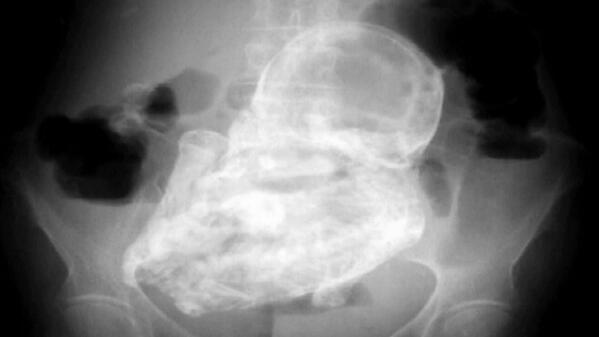

@ABC: Elderly woman informed pain in her stomach caused by 40-year-old "stone" fetus: http://abcn.ws/19mWDZN pic.twitter.com/weSejjlhLQ” OMG

@ABC: Elderly woman informed pain in her stomach caused by 40-year-old "stone" fetus”@YooGabbaGabi @TaraShea04 SHE HAD A STONE BABY!Thanks. Twitter will use this to make your timeline better. UndoUndo